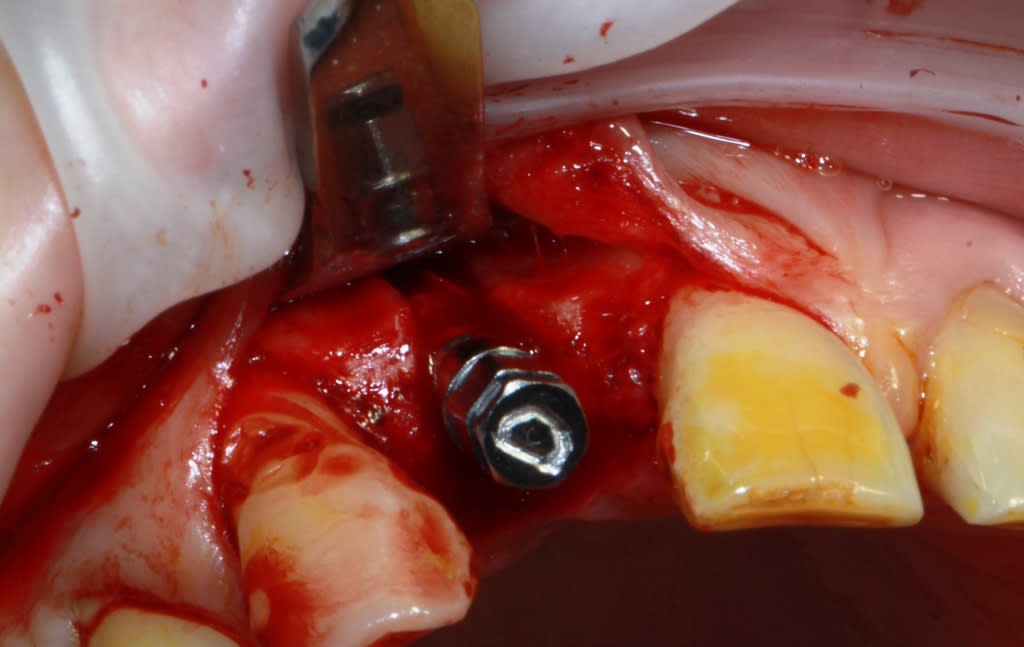

Thomas, tu as un plan pour guider dans un cas comme ça?

ou comment remplacer 12 avec soucis vestibulaire, par un implant, sans greffe, sans ROG, juste avec les mimines....?

vue de l’intérieur..

Pas de comblement pour epaissir le rempart vestibulaire ? tu ne crains pas une résorption dans le temps de ce spongieux amené en vestibulaire ?

d'expérience tu mets aussi un matériau non résorbable en complément en vest ibulaire sinon DANGER

Et bien pas du tout...Fouad Khoury pratiques comme ça depuis longtemps ( mieux que moi...) et pour ma part j'ai des cas de 89 qui vont toujours très bien et même si ça peut arriver je ne compte aucun cas d'échec dans ce type d'intervention.

Nul besoin de poudre de perlimpimpin ni autre artifice.